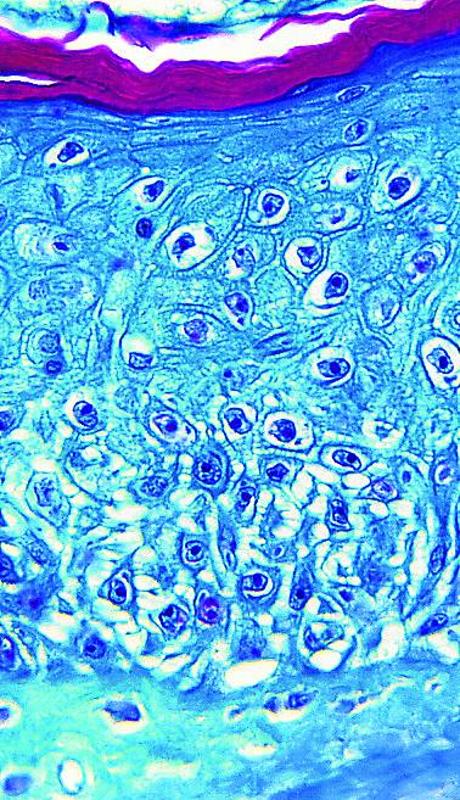

Lesiones en la piel de un paciente con viruela del mono. Efe